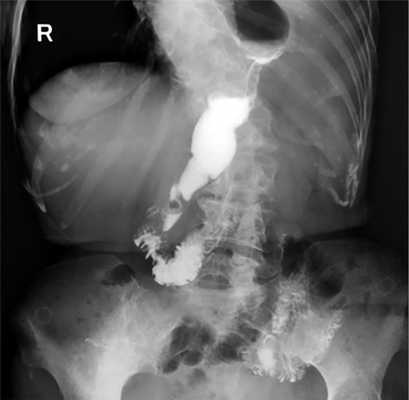

Больная Д., 61 год, поступила в клинику с жалобами на затруднение прохождения твердой и жидкой пищи по пищеводу, снижение массы тела на 18 кг за 6 мес, слабость, утомляемость. По данным комплексного обследования диагностирован первично-множественный синхронный рак: рак пищеводно-желудочного перехода (рис. 3), осложненный дисфагией и рецидивирующим кровотечением из опухоли (Hb 87 г/л); гистологически — умеренно-дифференцированная аденокарцинома; аденокарцинома толстой кишки in situ. Сопутствующие заболевания: гипертоническая болезнь I стадии, II степень. Хроническая сердечная недостаточность II стадии, II ФК по NYHA. Синусовая тахикардия. Хроническая болезнь почек — С3а. Гиперлипидемия. Облитерирующий атеросклероз сосудов нижних конечностей. Хроническая венозная недостаточность нижних конечностей.

Рис. 3. Рентгенограмма пищевода и желудка больной Д. с кардио-эзофагеальным раком.